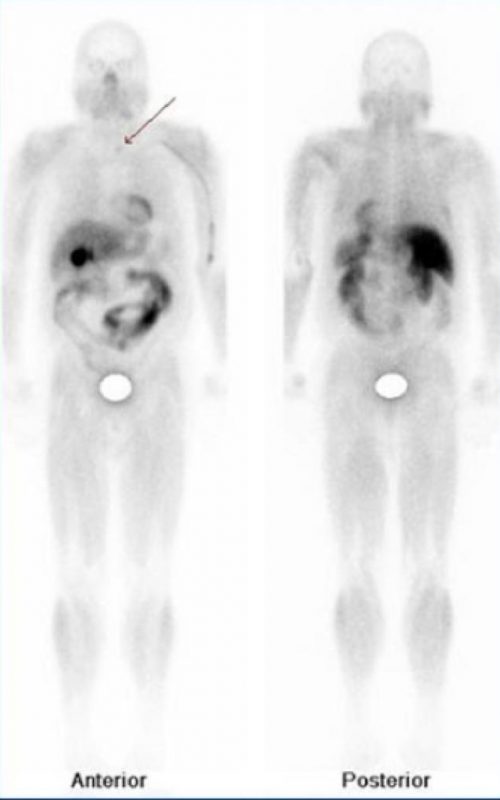

Rastreo con MIBI